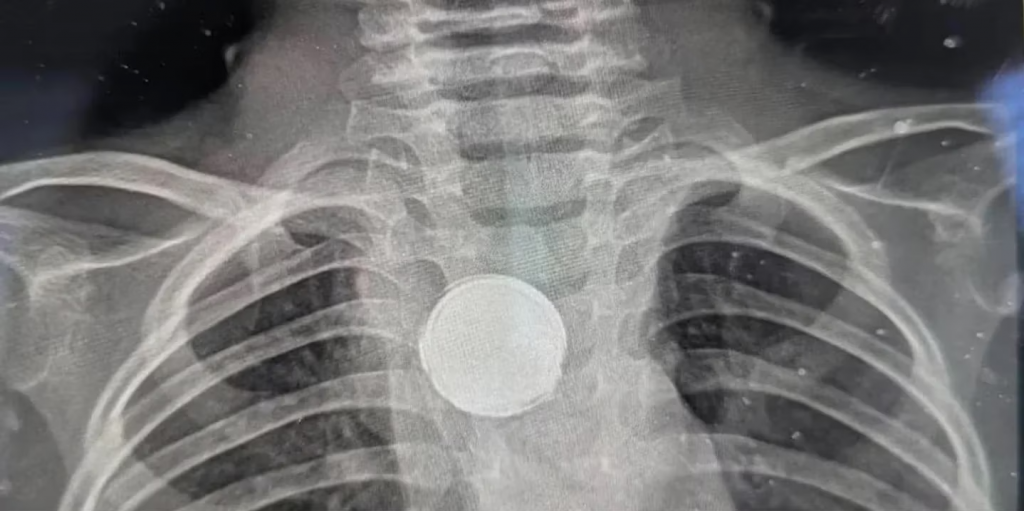

A través de una radiografía de tórax, el nuevo médico que atendió al nene encontró lo que le sucedía. “Les vi poner mirada extraña”, recordó la mamá de Luke y, al ver las imágenes, comenzaron a preguntar si existía la posibilidad que el se haya tragado una moneda o un botón.

De inmediato, lo trasladaron de urgencia a un hospital para determinar de qué se trataba el objeto que veían en los estudios. Según explicó la mamá, los profesionales decían: “No hay forma de que sea una pila porque comienzan a corroerse en tan solo dos horas”

En esta misma línea, Erica la mamá señaló: “Dijeron que tenía algo plateado en el pecho, pero que sería peligroso sacar ese objeto sin una cirugía completa”. De esta manera, se llevó adelante la intervención quirúrgica correspondiente y encontraron que la pila estaba envuelta en una cinta aislante, lo que permitió que no se degrade y le salvó la vida al menor de edad.